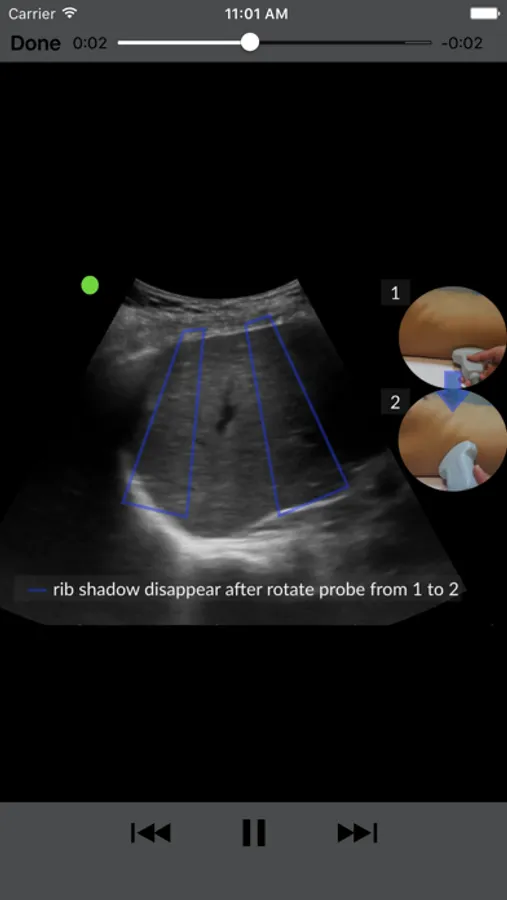

- High quality ultrasound images and video references. The images include ‘click-for-label’ function for quick scans of the organs and areas to look for abnormality. The images can be enlarged as well. Video can be click and play to compare on bedside.